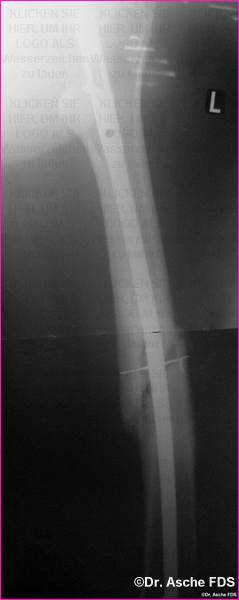

Osteosynthese mit PFN

Die Osteosynthese war primär nicht belastungsstabil

Nach Belastungsbeginn kommt es zur Varisierung durch

den dünnenNagel

Bereits primär lag ein Drehfehler von 13° vor.

Der Patient konnte nach 6 Monaten nicht schmerzfrei laufen.